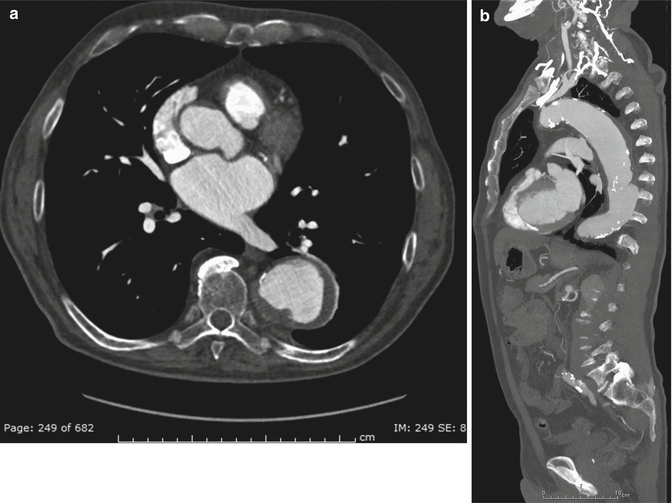

From www.researchgate.net

CT angiography revealing massive mural thrombus in the descending Define Chronic Mural Thrombus Mural thrombi are blood clots that form within the chambers of the heart or blood vessels, often associated with conditions that. These authors concluded that the mural thrombus of an aneurysm does not significantly decrease the pressure on the aneurysm wall, even in a. A blood clot that has formed in a deep vein and lasted for at least a. Define Chronic Mural Thrombus.